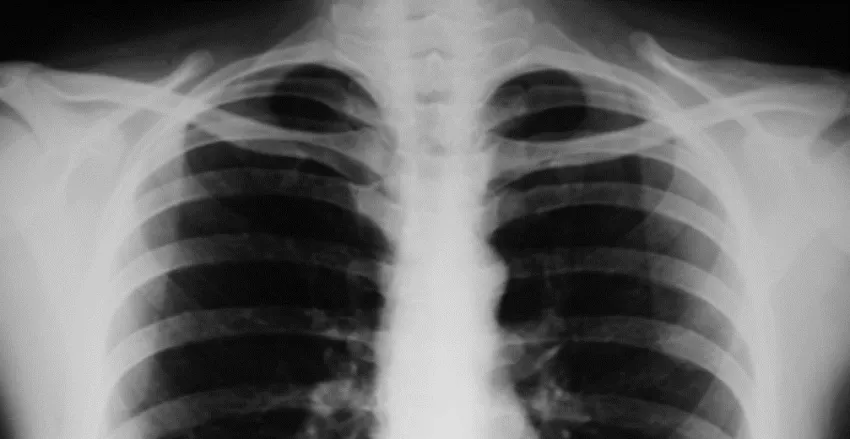

Lung COPD Asthma

Das Spektrum der chronischen Lungen- und Atemwegserkrankungen ist groß: Die Weltgesundheitsorganisation (WHO) zählt Asthma bronchiale oder die chronisch obstruktive Lungenerkrankung (COPD) ebenso dazu, wie insgesamt 64 weitere Indikationen1. Diese zählen mittlerweile zu den dritthäufigsten Todesursachen in Deutschland2. Die Zahl der Betroffenen steigen3 und somit die Kosten für das deutsche Gesundheitssystem.

Bestehen Beschwerden über einen längeren Zeitraum, ohne dass eine Besserung eintritt, werden Lungen- und Atemwegserkrankungen als chronisch bezeichnet. Infolge ihrer hohen direkten und indirekten Kosten sowie einer hohen Morbidität nehmen diese eine besonders tragische Rolle ein: